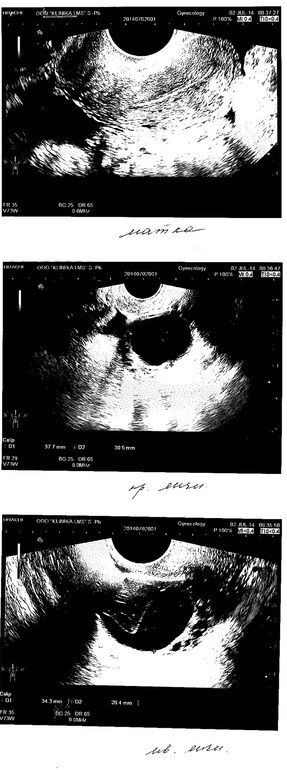

Сегодня

на УЗИ мне насмотрели предположительно кисты обоих яичников, по словам

узистки - большие. Консультаций и диагнозов она не дала, т.к. говорит,

что узист не имеет на это права. Сказала, что из-за этого могут быть

перебои.

Делали на 7 ДЦ.

Меня волнуют эти предполагаемые кисты, а также эндометрий 2 мм.